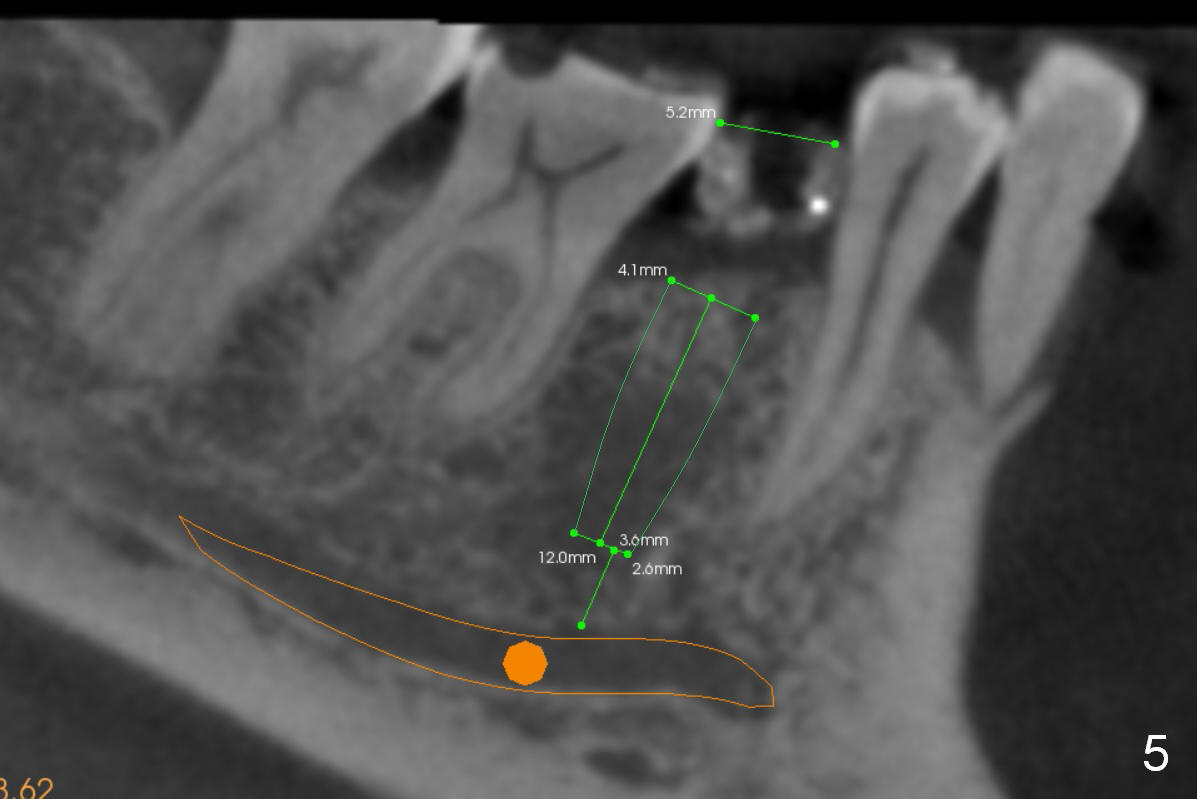

A 56-year-old man has long-termed partial edentulism (#2,5,14,15 (not shown),29, Fig.1). There is supraeruption of the opposing teeth (Fig.1 arrows). If an immediate provisional is provided, it should have plenty of clearance to avoid micromovement of the implant. Once the implants at #2,5, and 29 osteointegrate, they will be used as anchorage for intrusion (Fig.2,3 arrows, segmental orthodontics).

The first implant will be placed at #29 (Fig.4,5). The pointed ridge will be flattened to start osteotomy (Fig.6,7 (surgical handpiece)). The buccolingual dimension of the flattened ridge should be ~ 6 mm. The initial depth will be 12 mm. Take the 1st PA. A restorative high speed handpiece may be needed to remove the enamel of the mesial surface of #30 and the distal surface of #28 to increase space for implant placement.